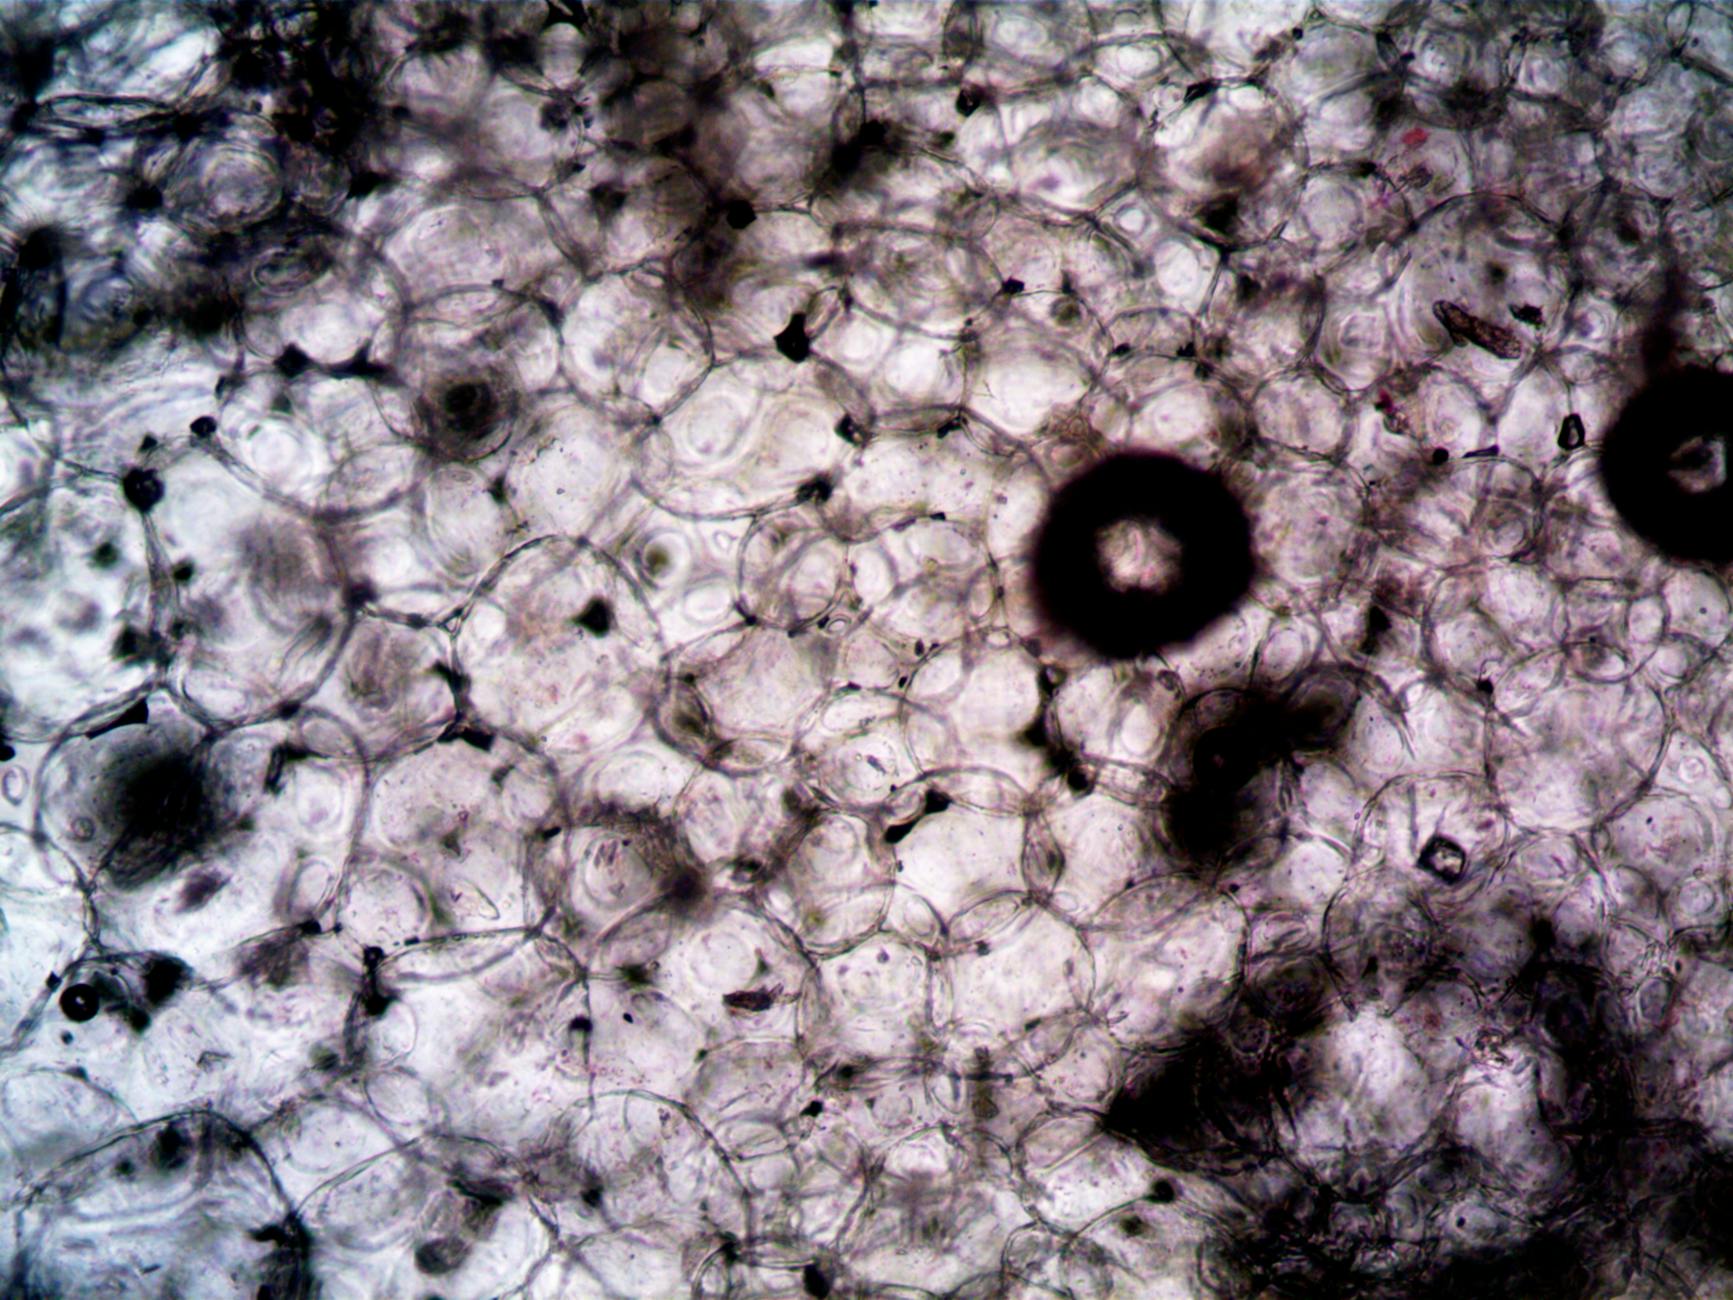

Istraživači iz VIB-KU Leuven Centra za biologiju raka i Francis Crick Institutea otkrili su kako metastatske stanice raka prisiljavaju zdrave plućne stanice da za njih proizvode lipide. Riječ je o alveolarnim tip II (AT2) stanicama, koje normalno proizvode surfaktant, ali ih metastaze reprogramiraju da aktiviraju ključne gene za sintezu lipida poput FASN i GPAM 1.

Ovaj proces omogućuje metastatskim stanicama da dobiju potrebne molekule za rast i prilagodbu u plućnom tkivu. Studija, objavljena u časopisu Cancer Discovery, koristila je prostornu analizu na miševima i uzorcima pacijenata kako bi dokazala da AT2 stanice u neposrednoj blizini metastaza značajno povećavaju proizvodnju lipida.

Ključni regulator ovog procesa je transkripcijski faktor SREBP-1, koji aktivira gene poput FASN-a, odgovornog za sintezu palmitata – esencijalne masne kiseline za rast tumorskih stanica 2. Istraživači su pokazali da selektivno isključivanje gena Fasn u AT2 stanicama ili sistemsko ciljanje na FASN i GPAM značajno usporava rast metastaza u plućima miševa.